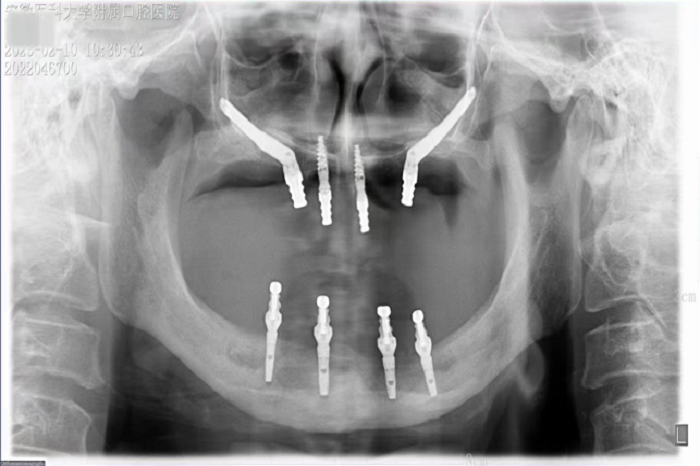

据悉,患者潘女士54岁,由于重度牙周炎导致全口牙齿缺失,严重影响面容及咀嚼功能,因颌骨严重萎缩无法进行活动义齿修复,遂来永利 种植科要求行上颌稳固的修复。通过检查发现潘女士上下颌骨骨量严重不足,经反复比对和考量,刘鑫主任制定了对患者上颌骨进行穿颧种植修复、下颌骨通过神经游离进行种植的方案。经过患者与家属深思熟虑后,接受了行穿颧种植术的建议。治疗组通过专业三维设计软件规划植体,口腔颌面外科和种植科专家共同完成了穿颧种植手术。患者术后第一天情况良好,无明显肿胀,精神状态佳。

穿颧种植是瑞典人发明的一种通过颧骨固定种植牙的技术,也是当今难度最高的种植技术。在传统种植领域,上颌骨极度萎缩及上颌骨部分切除患者的种植手术受到极大的限制,一方面需要大量植骨,易增加种植失败的风险,另一方面也会延长种植戴牙时间。因此对于这类患者,在全身健康状况良好的条件下,具备条件的种植机构即可采用穿颧种植手术,不仅能避免术中大量取骨、植骨的风险,也能大大缩短患者种牙时间。